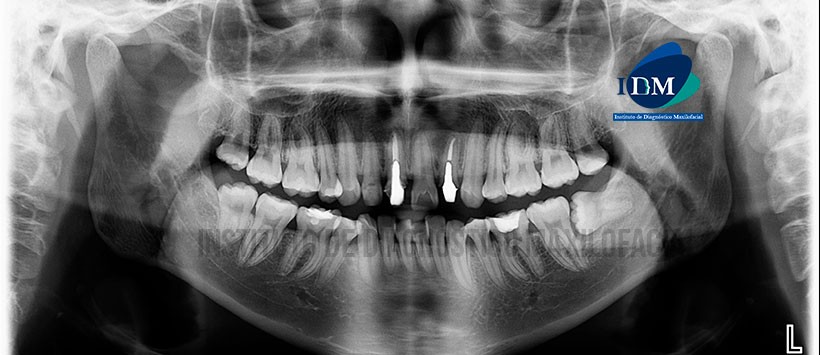

En la radiografía panorámica (Figura 1) se aprecia obturación de conductos radiculares y espigo muñón colado en piezas 11 y 22; la pieza 36 presenta restauración coronaria con compromiso de cámara pulpar, imagen radiolúcida en tercio cervical de raíz mesial con aparente comunicación hacia la zona de furca donde se observa proceso osteolítico.